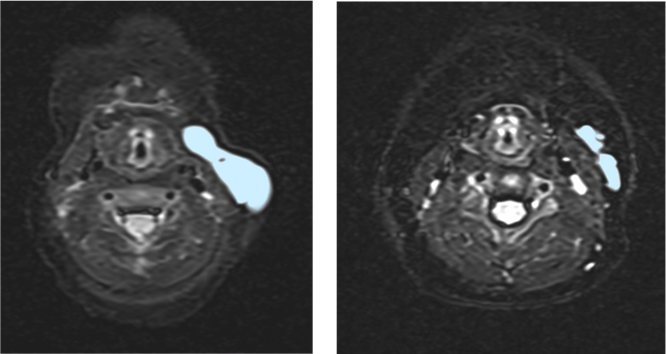

本研究では、体重25kg 以下の小児19 人に越婢加朮湯を6 か月間投与し、その効果を調べました。MRI により画像検査を行ったところ、52.6%の症例で病気の部分が20%以上縮小し、顔や首回りでは83.3%の小児に効果が見られました。副作用は軽度なものが多く、重い副作用を発症したのは1 人だけでした。また、薬の継続率も高く、約9 割が実際にきちんと飲まれており、多くの子どもが継続して治療を受けら

れたことがわかりました。